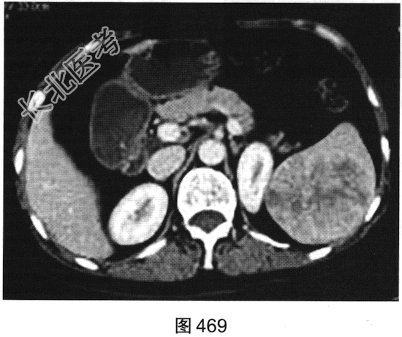

- [材料题] 患者男性,47岁,因“左上腹隐痛6个月余”就诊。腹部B超发现脾脏占位。

- 多项选择题2.[提示]患者行CT动态增强扫描,如图467~图469所示。对CT图像描述正确的是( )

A、病灶内见条索状钙化灶

B、病灶动脉期无强化

C、CT平扫呈不均匀稍低密度

D、左肾被病灶侵犯

E、病灶门脉期显著强化

F、病灶边界清晰,具有包膜